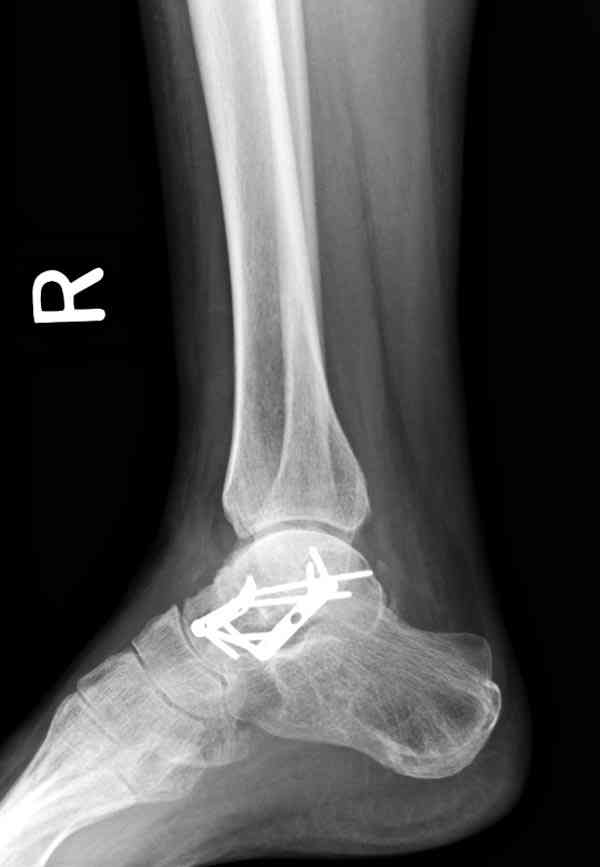

И второй случай из недавней ташкентской практики, (извините за качество ренгенограммы и только в одной проекции) случай падения с высоты (кстати моего друга - известного киноактера) - открытый

смещенный перелом тарана, с переломом переднего края дистального эпиметафиза большеберцовой кости.

При поступлении в приемной сделана первичная обработка с ушиванием открытой латеральной раны и вытяжением за пятку.

Из-за отсутствия времени пришлось оперировать на второе утро, из материала, что имеем на месте, фиксирован двумя шурупами, а третий-это контур сломанного жойстика в 4 мм. На дистальный медиальный конец тибиа antiglide 3.5 мм пластина. Через пару дней выписан и несмотря на предупреждение, самостоятельно начал нагрузку в 4 недели, время не ждет, снимается в боевике в Росийской Федерации.

Djoldas Kuldjanov, MD